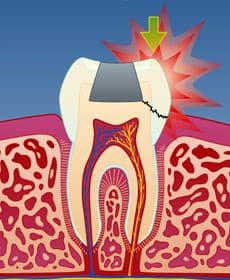

I tenner med store fyllinger er tannsubstansen rundt fyllingen svekket. Når man tygger, kan det etter hvert utvikles tynne sprekker i tannen. Disse sprekkene utvikler seg under fyllingen og forløper vanligvis på skrå bort fra tann-nerven (fig. 1). Infraksjonen kan imidlertid også gå inn til nerven (fig. 2) eller til og med dele tannen i to (fig. 3).

I de tilfeller sprekkdannelsen deler tannen i to, kan det være nødvendig å trekke tannen.